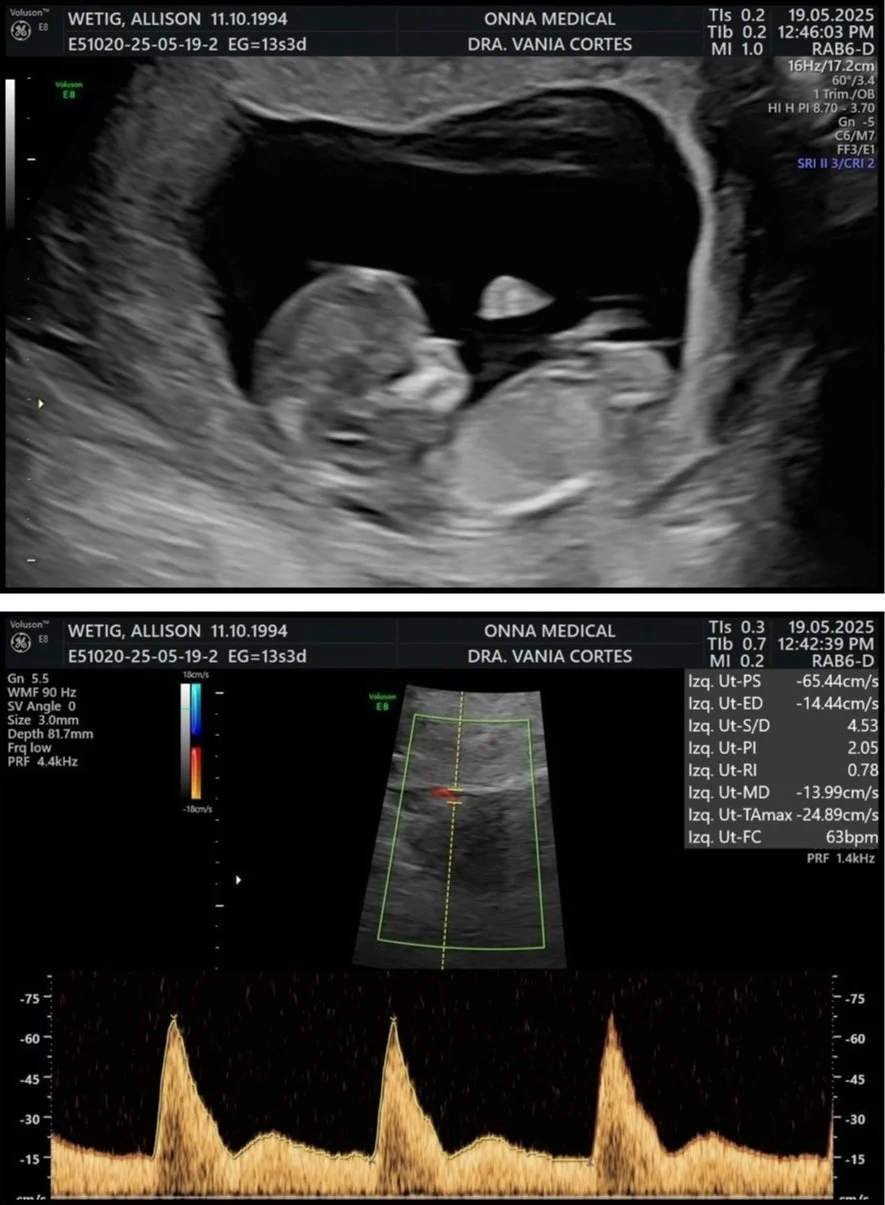

There isn’t a lot of top tier medical care in Tulum so we thought we’d make a special trip to Mexico City for our first ultrasound. I did a lot of research and found Onna Medical through a Reddit comment. The comment spoke really highly of the facility, English speaking staff and overall experience. I absolutely hate being in doctor’s offices. I am really squeamish so I wanted to go somewhere that I knew would be clean, welcoming and accommodating to English speaking.

All that aside, the first ultrasound went as good as it could have. She gave us an A+ which was incredibly relieving. My favorite part was hearing baby’s heartbeat because it made all of it feel real.